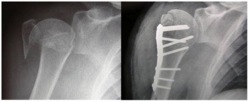

If the bones are allowed to heal with a step in the articular cartilage they will become painful and stiff which will result in poor function. The decision to operate will depend on the way the bone has broken, the quality of the bone, the needs of the patient and the expertise of the surgeon. Our most common operation for this type of fracture is the locking plate. Through a 10-15cm incision the bone pieces are put back together and held with a plate and some screws. This is special plate which locks the screws in place and has revolutionised the treatment of osteoporotic fractures.